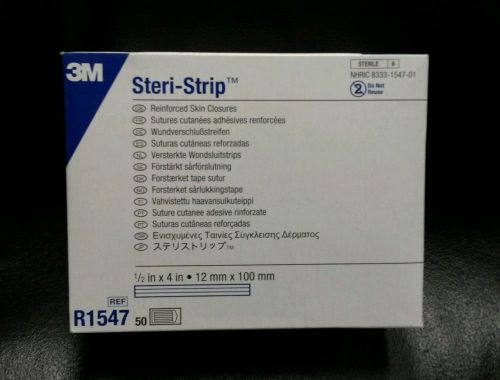

3M Steri-Strip R1547 Skin Closures box of 50 exp: 2016-03